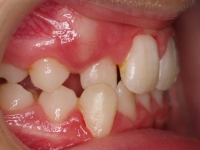

El paciente A.J. de 11 años, acude a nuestra consulta con apiñamiento maxilar importante. El canino lateral (12) está en mordida cruzada. Presenta una Clase II molar y canina, y la línea media está desviada. Se realizó un tratamiento con brackets autoligables metálicos de smartclip 022. La duración del tratamiento fue de 22 meses.

El paciente actualmente ha terminado el tratamiento con brackets y lleva una contención fija de 2-2 en maxilar y 3-3 en mandibular; para complementar también lleva una férula ESSIX durante la noche.